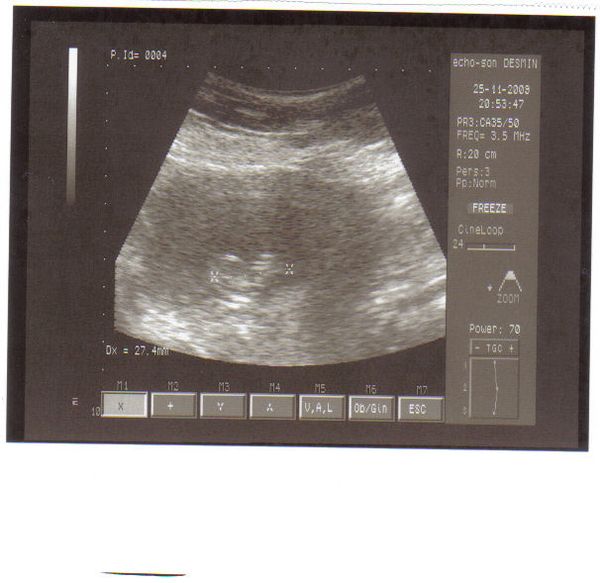

Megjöttem a dokitól, minden rendben van, méhszájam teljesen zárt, babszemjankóm 27,4 mm hosszú és gyönyörűen ver a szívecskéje.Olyan jó volt látni, hiába 4. gyermek, az uh mindig egy nagy élmény.

Úgy néz ki, hogy a méhlepény most a hátsó falon tapad, ami jó is(bár még változhat) mert elől van a császáros heg.

Megbeszéltük, hogy valszeg megint császár lesz, de ad kb 3-4 óra vajúdást. És ha vág, akkor egyben megcsinálja a lekötést is. Emiatt szomorú vagyok, de apa hallani sem akar több lurkóról.

Kaptam képet is, de nem valami jó a gépe, így nem sok minden látszik rajta. Bal oldalon van a buksi kezdemény, és jobbra pedig lesznek a végtagok. Ő már látta a végtagkezdeményeket(én nem), de majd 2 hét múlva a kórházi szuper gépen már szupi képet fogok hozni.

Íme "kid number 4"